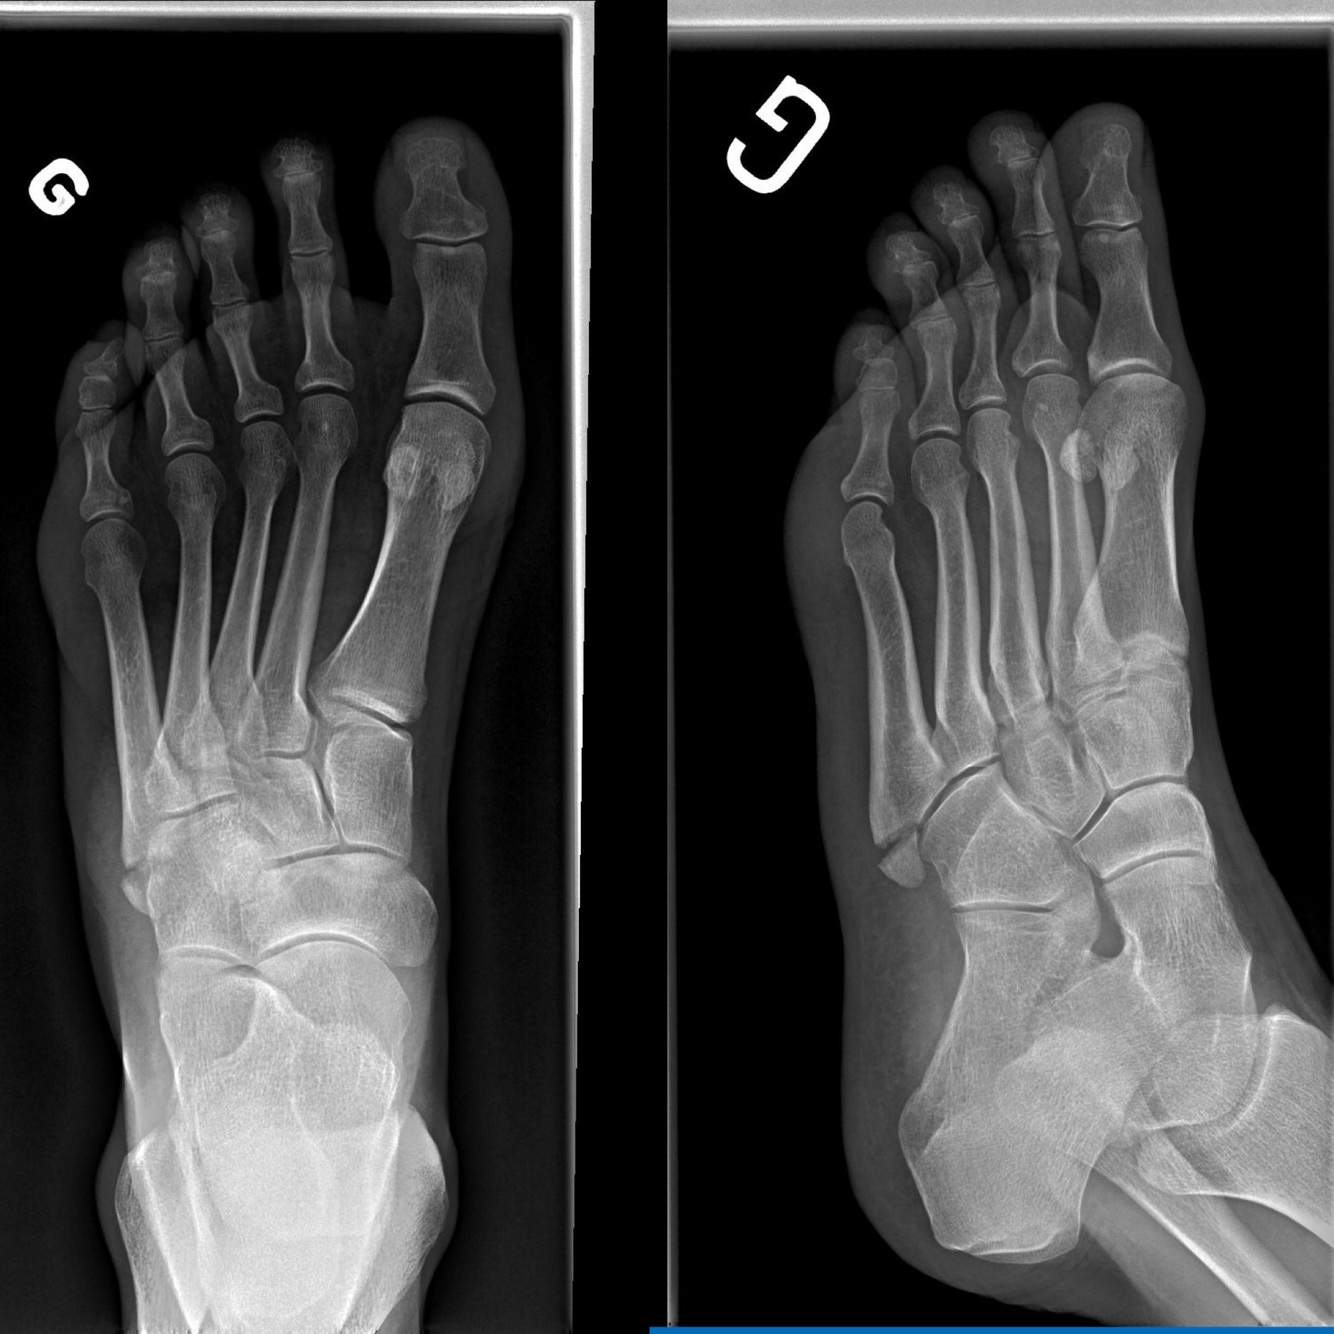

Q

Quelle vue?

Évalue quoi ?

A

Projection oblique

Évaluation de:

• Utile pour les luxations et subluxation médio-

tarsiennes, pour enlever certaines surimpositions (ex les os sésamoïdes) et visualiser la base du 5ième métatarsien

• Le bord interne du 3ième méta est aligné avec le bord interne du 3ième cunéiforme

• Le bord interne du 4ième méta est aligné avec le bord interne du cuboïde

• Doit toujours être demandée post trauma (critère Ottawa +)